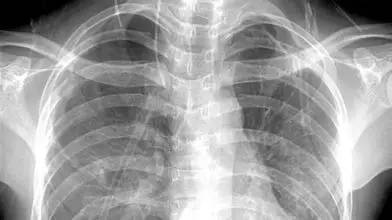

X光:像把面包壓扁了看

X光會穿過人體,遇到被遮擋的部位,底片上不會曝光,洗片后這個部位就是白色的。

就像一片面包或一塊棉花,看不到里面的纖維紋理,但用手壓癟了會清晰一些。X光最大缺點是受制于深淺組織的影像相互重疊和隱藏,有時需要多次多角度拍攝X光片。

3、胸部——粗看X光片,細(xì)看CT

X光胸片可粗略檢查心臟、主動脈、肺、胸膜、肋骨等,可以檢查有無肺紋理增多、肺部鈣化點、主動脈結(jié)鈣化等。

胸部CT檢查顯示出的結(jié)構(gòu)更清晰,對胸部病變檢出敏感性和顯示病變的準(zhǔn)確性均優(yōu)于常規(guī)X光胸片,特別是對于早期肺癌確診有決定性意義。但是CT檢查的輻射劑量高于X光。核磁對于肺部疾病的診斷,應(yīng)用非常有限。